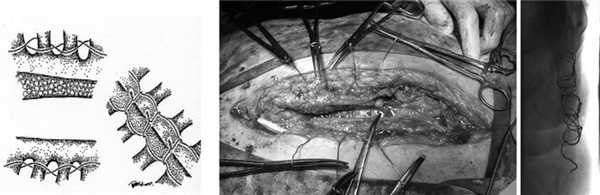

Наиболее часто (у 24 из 48 больных) выполняли операцию - хирургическую обработку раны с резекцией пораженных участков грудины или реберной дуги, реостеосинтез грудины, закрытое проточно-промывное дренирование. При этом производили полное раскрытие стернотомной раны, удаление всех инородных материалов, некротизированных тканей и выполняли стабилизацию грудины металлической проволокой по Robicsek [8] (рис. 1). Рисунок 1. Закрытие грудины по Robicsek.

Варианты пластического замещения дефектов грудины с использованием большой грудной мышцы представлены на рис. 2 и 3. Рисунок 2. Бипекторальная пластика с широким косопоперечным доступом для мобилизации мышечного лоскута (в дальнейшем использовали дополнительный разрез в грудинодельтовидной ямке или отсекали мышцу без дополнительного разреза за счет широкого разведения раны). Рисунок 3. Мобилизация и пластика дефекта грудины правой большой грудной мышцей с дополнительным разрезом в грудинодельтовидной ямке.